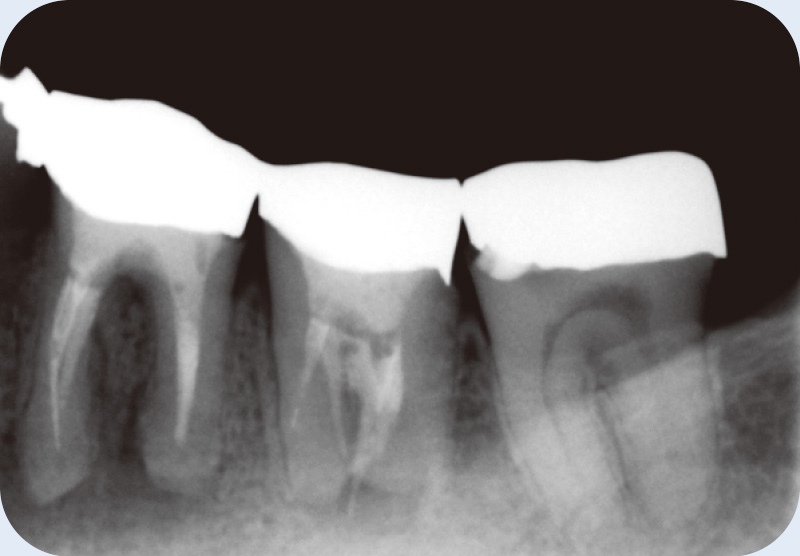

症例紹介② 根尖が開大した難治性根尖性歯周炎 菅谷 勉先生

![[写真] CT](/academic/dentalmagazine/wp-content/uploads/sites/2/2025/11/195-3_photo08.jpg)

CTで見ると、近心頰側根も遠心頰側根にも根尖部病変があり、口蓋根は吸収していて、根尖孔が拡大している。この状態になると、根管洗浄を行っても十分細菌が取り切れず、治癒が難しくなる。(Veraviewepocs 3Dfにて撮影) -